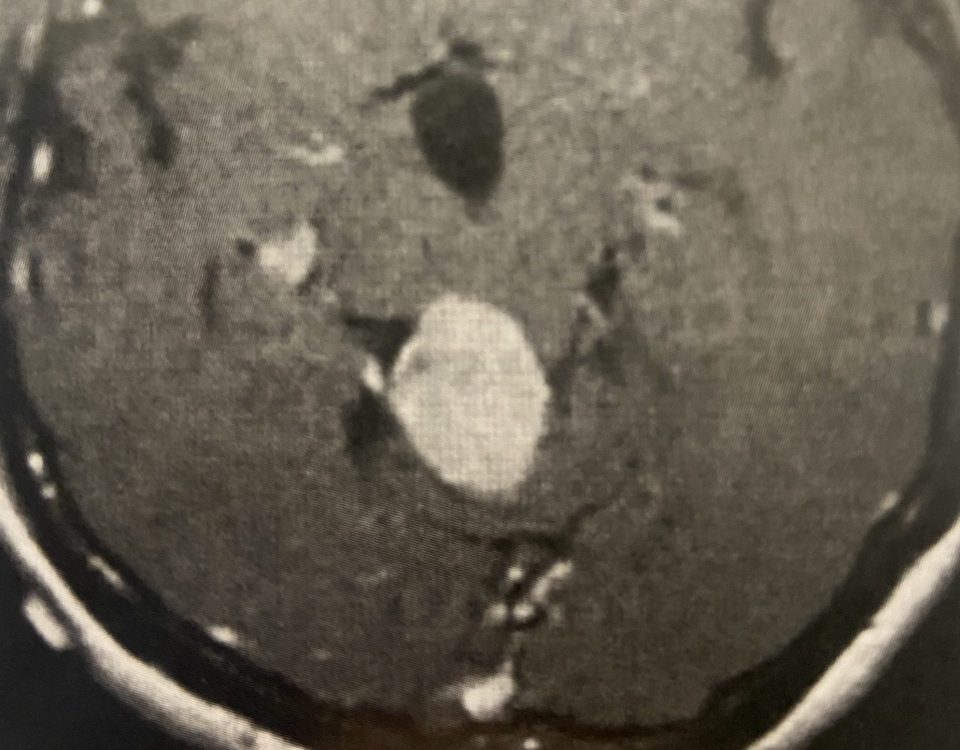

This is a 57-year-old woman with new onset memory problems and gait difficulty. MRI demonstrated a 3 cm tumor in the pineal region, most consistent with […]

MRI with gadolinium confirmed the likely diagnosis of convexity meningioma, a benign neoplasm of the meninges. Given the location of the tumor, angiography and embolization were […]